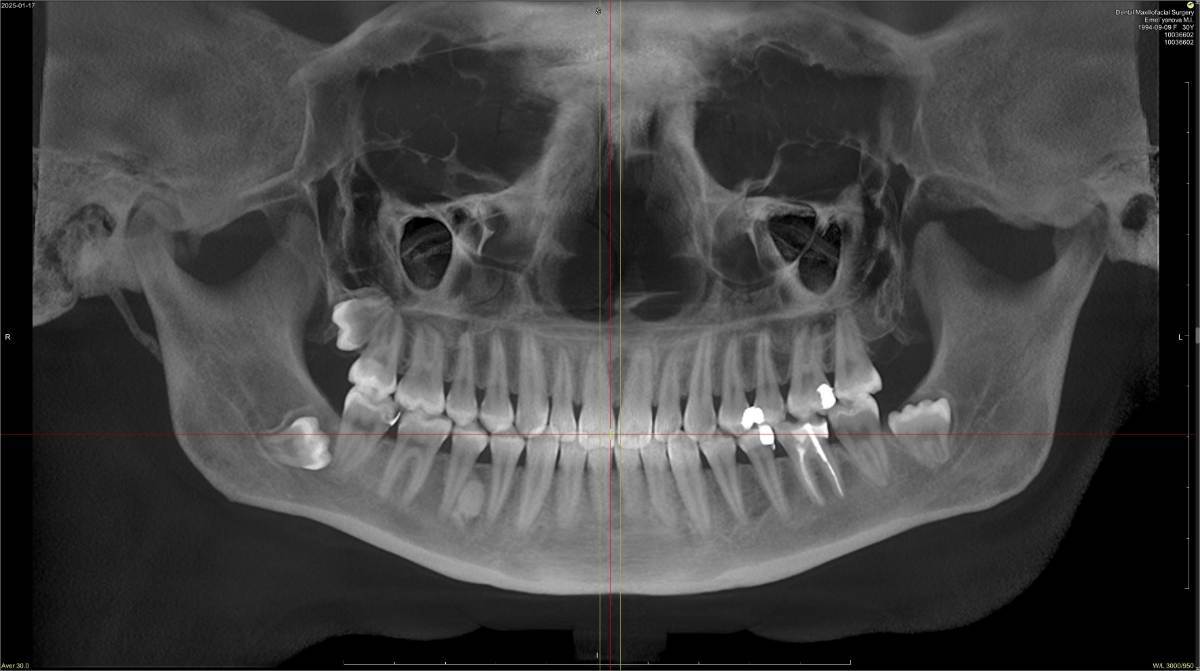

Светлое пятно в кости на КЛКТ

Делала КЛКТ, на нижней челюсти есть светлое пятно между четверкой и пятеркой. Что это может быть, к какому врачу обращаться?

Снимок прикладываю.EmelyanovaM.I.(1).jpg.0ab2567cc5c805363c85fcc1678b0a68.jpg

Здравствуйте. По этому снимку похоже на эностоз. Если это он, то лечения не требует. Лучше выложите архив кт, либо добавьте разных срезов.